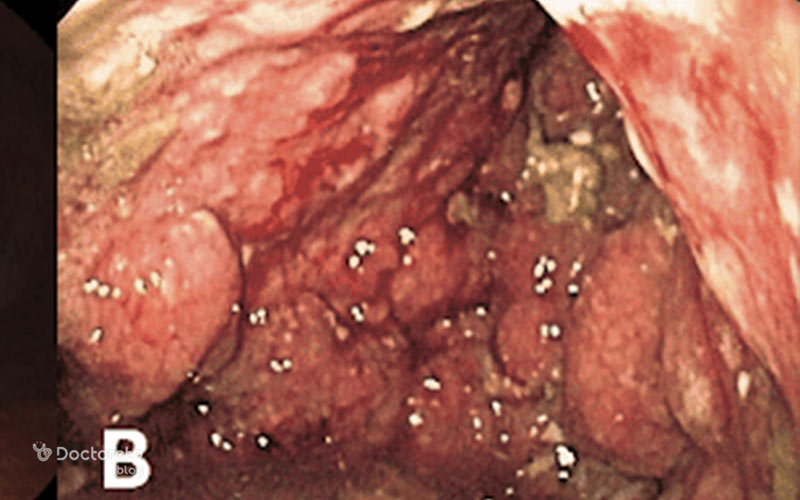

عکس زخم سرطان معده بدخیم

زخمهای ناشی از سرطان معده ممکن است در ابتدا شبیه به زخم معده معمولی باشند، اما با گذشت زمان شکل، اندازه یا حالت آنها تغییر میکند. حتی ممکن است علامت پیشرفتهتری از بیماری باشند. این نکته اهمیت تشخیص درست و سریع را بیشتر میکند. در ادامه تصویری از زخم ناشی از سرطان معده بدخیم را مشاهده میکنید.